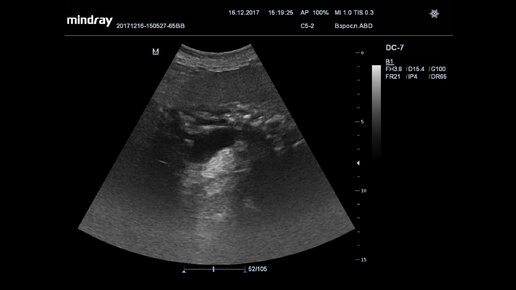

Ультразвуковая диагностика (УЗИ). Доктор Иогансен. Видеопримеры. Выпуск 43. Хронический панкреатит.